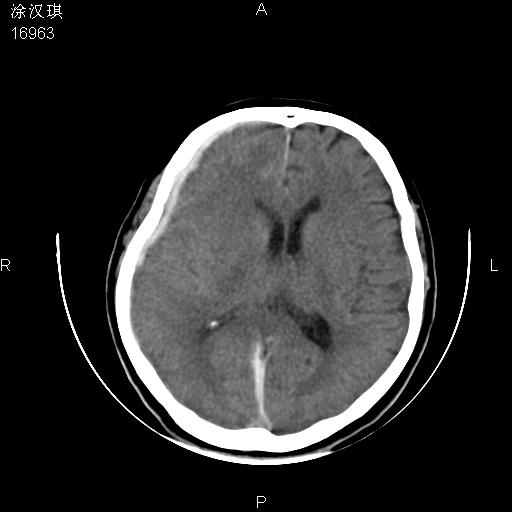

以下是引用chinazhouhua在2008-5-1 12:06:00的发言:[br]影像上来看,这是个典型的硬膜下血肿,包括右侧额颞部、大脑镰下、小脑幕下,而且在右侧额颞顶枕部、大脑镰下没看到高密度出血向脑沟内延伸,但是小脑幕下硬膜下有时候和蛛血不是很好鉴别,而且硬膜下很多时候伴有蛛血,往往在复查的时候出来,所以这种病人还是应该考虑硬膜下血肿伴有蛛血。

以下是引用zsl6918在2008-5-1 15:34:00的发言:[br]本病例主要表现为急性硬膜下血肿。